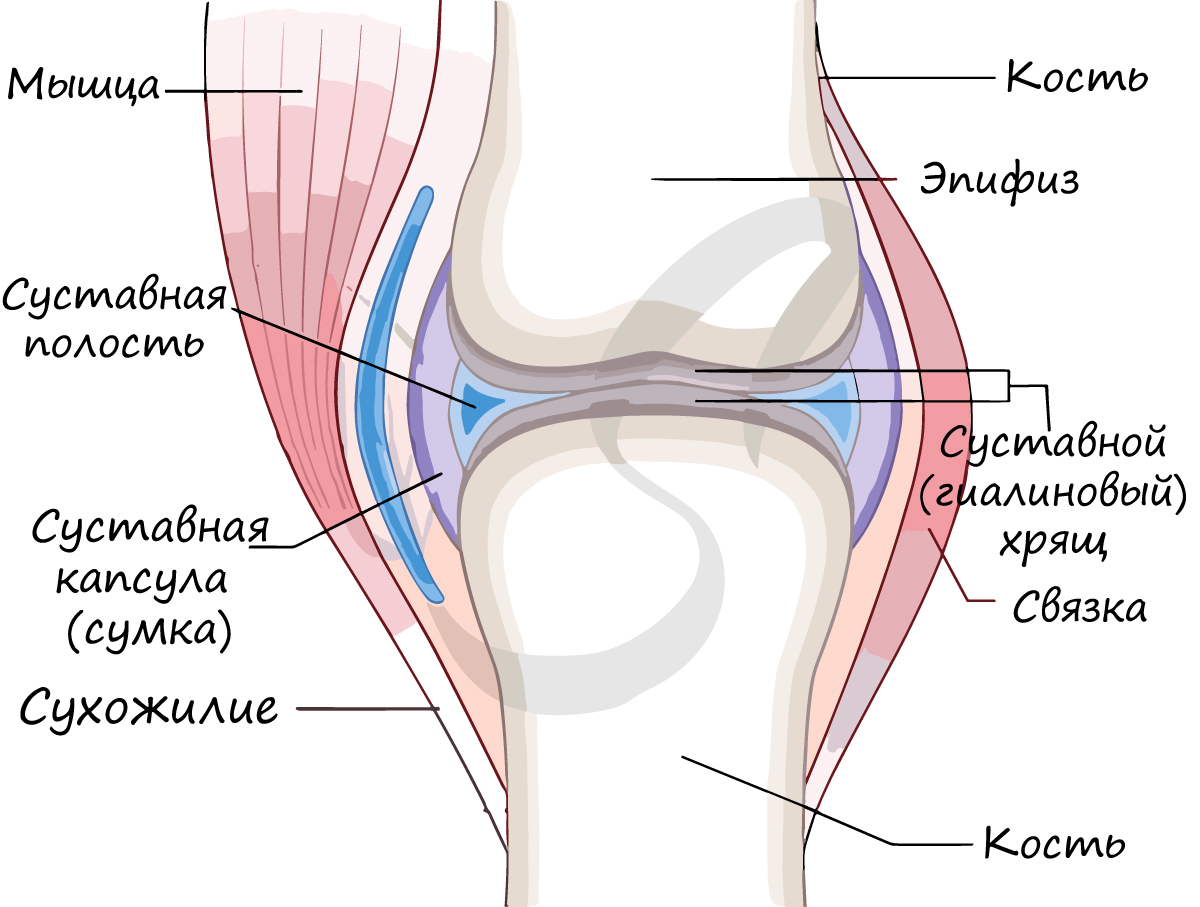

Кость состоит из костного вещества, костного мозга и надкостницы, а также имеет разветвленную сеть кровеносных сосудов и нервов, как показано на рисунке. Длинная бедренная кость состоит из диафиза и двух выпуклых эпифизарных концов. Поверхность каждого эпифизарного конца покрыта хрящом и образует гладкую суставную поверхность. Коэффициент трения в пространстве между хрящами в месте соединения сустава очень мал, он может быть ниже 0.0026. Это самый низкий известный показатель силы трения между твердыми телами, что позволяет хрящу и соседним костным тканям создать высокоэффективный сустав. Эпифизарная пластинка образована из кальцинированного хряща, соединенного с хрящом. Диафиз представляет собой полую кость, стенки которой образованы из плотной кости, которая является довольно толстой по всей ее длине и постепенно утончающейся к краям.

Соединения костей

Суставная сумка (капсула) крепится к суставным поверхностям или в их близи, окружает суставную полость (щелевидное пространство). Суставная сумка изнутри покрыта синовиальной оболочкой, которая секретирует синовиальную жидкость. Синовиальная жидкость заполняет полость сустава, питает сустав, увлажняет его, устраняет трение суставных поверхностей.

Подвижно в скелете человека соединены: нижняя челюсть + височная кость, ключица + лопатка (сустав малоподвижен), бедренная кость + тазовая кость (тазобедренный сустав), плечевая кость + локтевая + лучевая (локтевой сустав), бедренная + большеберцовая + надколенник (коленный сустав), голень и стопа (голеностопный сустав = большеберцовая + малоберцовая + таранная кости), фаланги пальцев.

В норме кости могут смещаться относительно друг друга в суставе, однако при травме, слишком резком и сильном движении это смещение может быть слишком сильным: в результате нарушается соприкосновение суставных поверхностей. В таком случае говорят о возникновении вывиха.

Хрящевая ткань является промежуточным звеном между соединительной тканью и костной. По сути, мы можем наблюдать постепенное развитие соединительной ткани в хрящ, где требуется функция хряща и дальнейшее постепенное окостенение хряща, где прочности хряща становится недостаточно. Уши и носовые ходы так никогда и не окостеневают.

Во внутриутробном развитии хрящевая ткань составляет около половины от всего скелета и постепенно замещается костной, достигая 2 % к зрелости. Это межпозвоночные диски, хрящи ребер, суставные хрящи, хрящи носа и уха, гортани, трахеи, бронхов. Суставные хрящи и межпозвоночные диски выполняют амортизационную функцию, также хрящевая ткань покрывает соприкасающиеся костные поверхности, что повышает их износоустойчивость.

Суставы являются наиболее сложным соединением. Кости, участвующие в образовании сустава, обычно имеют схожие по форме поверхности, так, например, тазовая кость имеет шаровидную головку, которая сочленяется с полулунным вдавлением вертлужной впадины и вертлужной губой. Для того чтобы такое соединения было долговечным при постоянной подвижности, эволюция предусмотрела более мягкое, хрящевое покрытие соединяющихся поверхностей и систему постоянной смазки и питания суставного хряща в виде синовиальной жидкости. Синовиальная жидкость продуцируется капсулой сустава, которая плотно приращена к надкостнице выше и ниже соединения. Капсула также регулирует объём суставной полости и выполняет изолирующую функцию, кровь через кровеносные сосуды поступает в капсулу, а в полость сустава поступает уже только самое необходимое из крови — синовиальная жидкость. В некоторых суставах для лучшего соответствия суставных поверхностей присутствуют дополнительные образования, например, диски между позвонками или мениски в коленном суставе. Так же сложные суставы, вроде коленного, укрепляются дополнительными внутрисуставными связками.